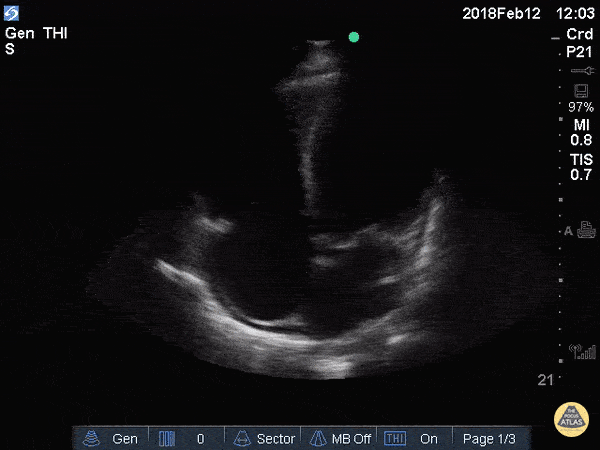

Apical 4 Chamber

• ANATOMIC LANDMARK: apex (5th interspace, ant ax line)

• Probe marker to the right

• SONOGRAPHIC LANDMARK: HEART

• Identify: LV, RV, LA,, RA, MV, TV

• Pericardium +/- Pericardial fluid